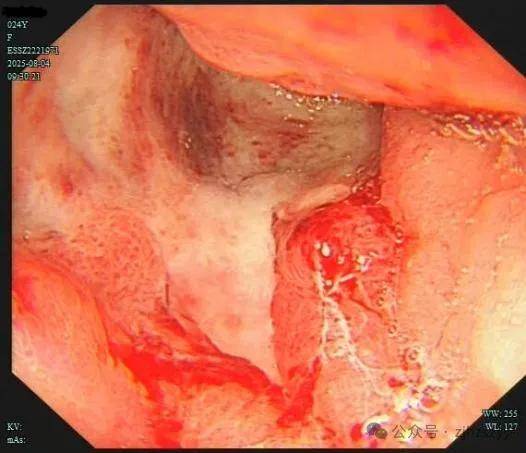

直到她开始频繁出现黑便,并在片场拍戏时几次呕血,才被同事紧急送往我院急诊。情况紧急,医生立即为小雯安排了急诊胃镜检查,发现她整个胃窦被一巨大的溃疡占据,黏膜组织变得僵硬、缺乏弹性,好似“皮革”一般。而随后的活检结果,更是给了这个年轻姑娘沉重一击——胃印戒细胞癌。

胃印戒细胞癌早期的隐匿性很强,在胃镜下表现也不明显,识别非常困难,可能表面看起来只是点、片状糜烂,而实际上已经多点生长。